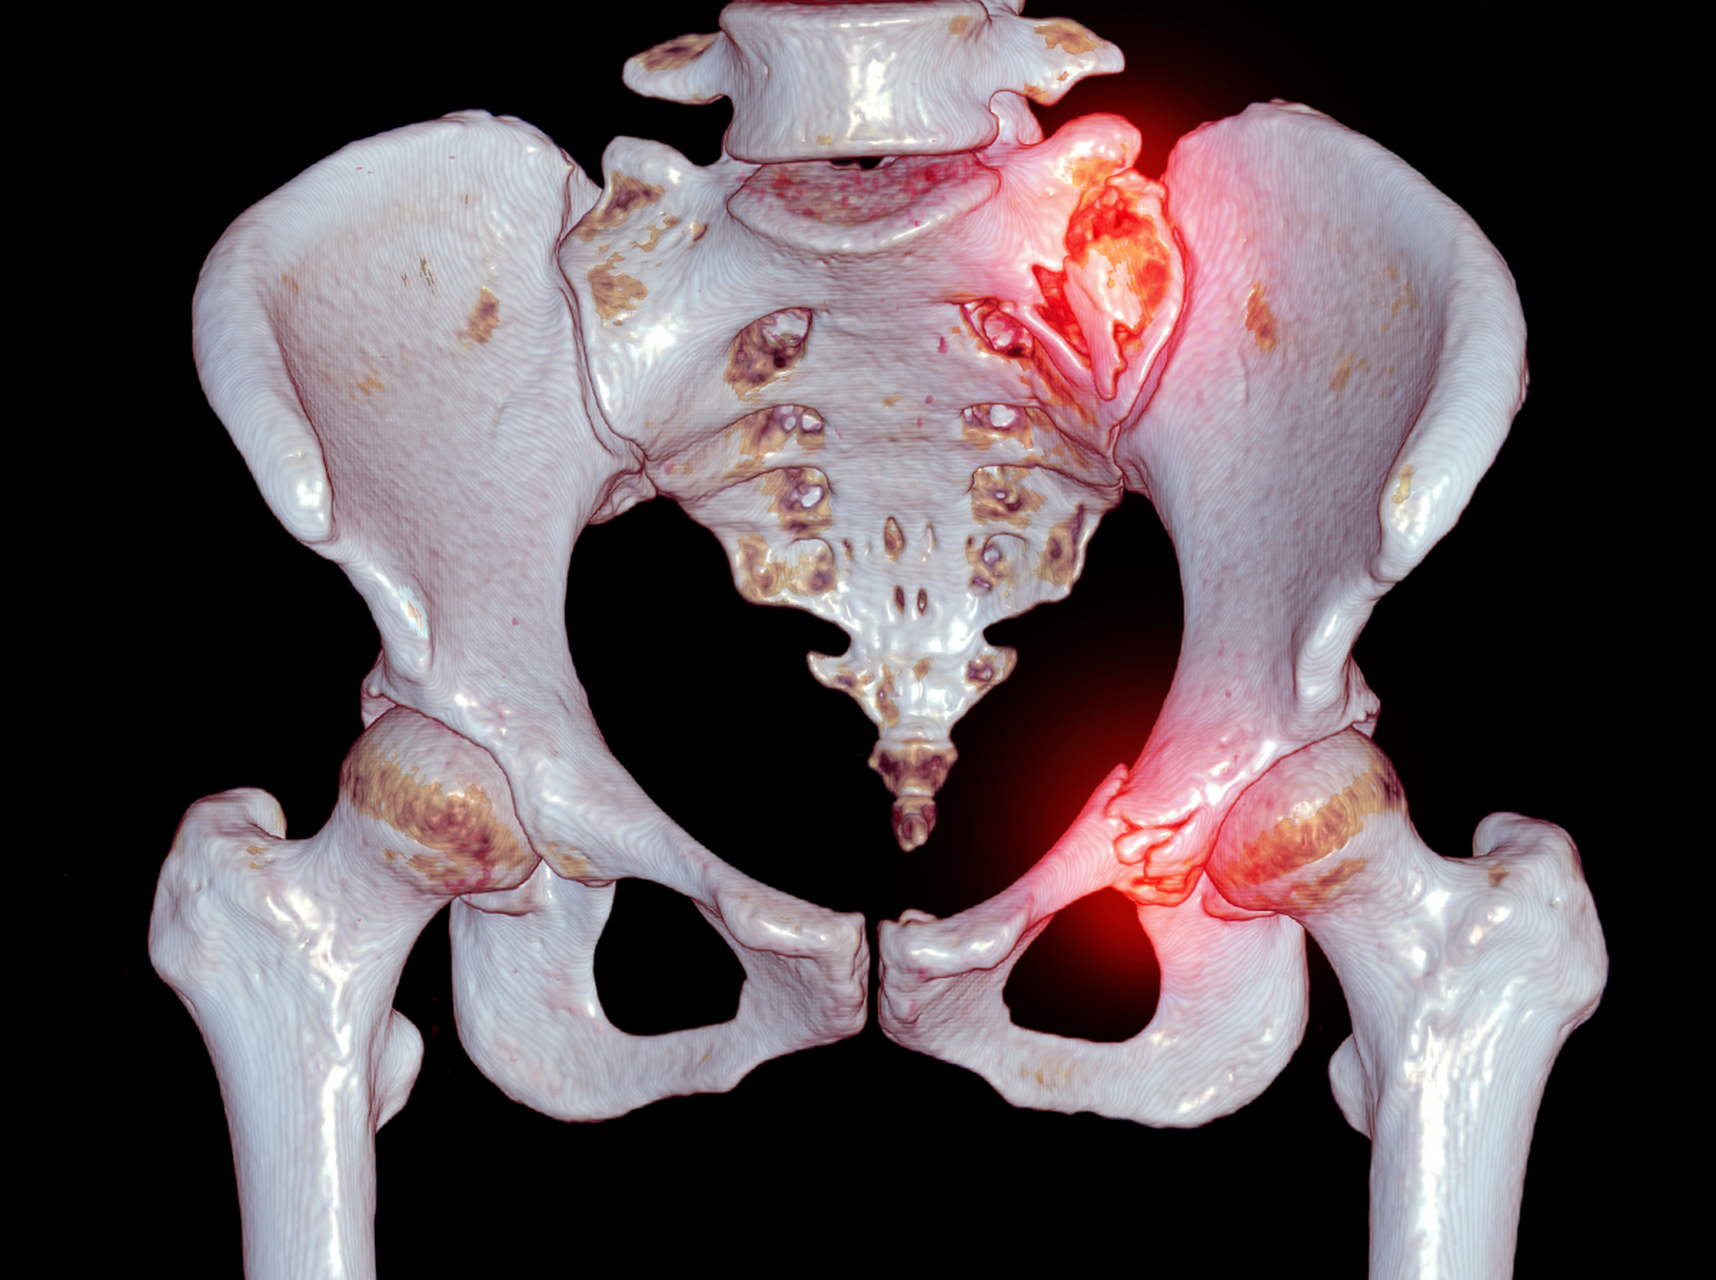

盆骨骨裂

哪位朋友医师能告诉我,我这个盆骨骨折了,严重吗?